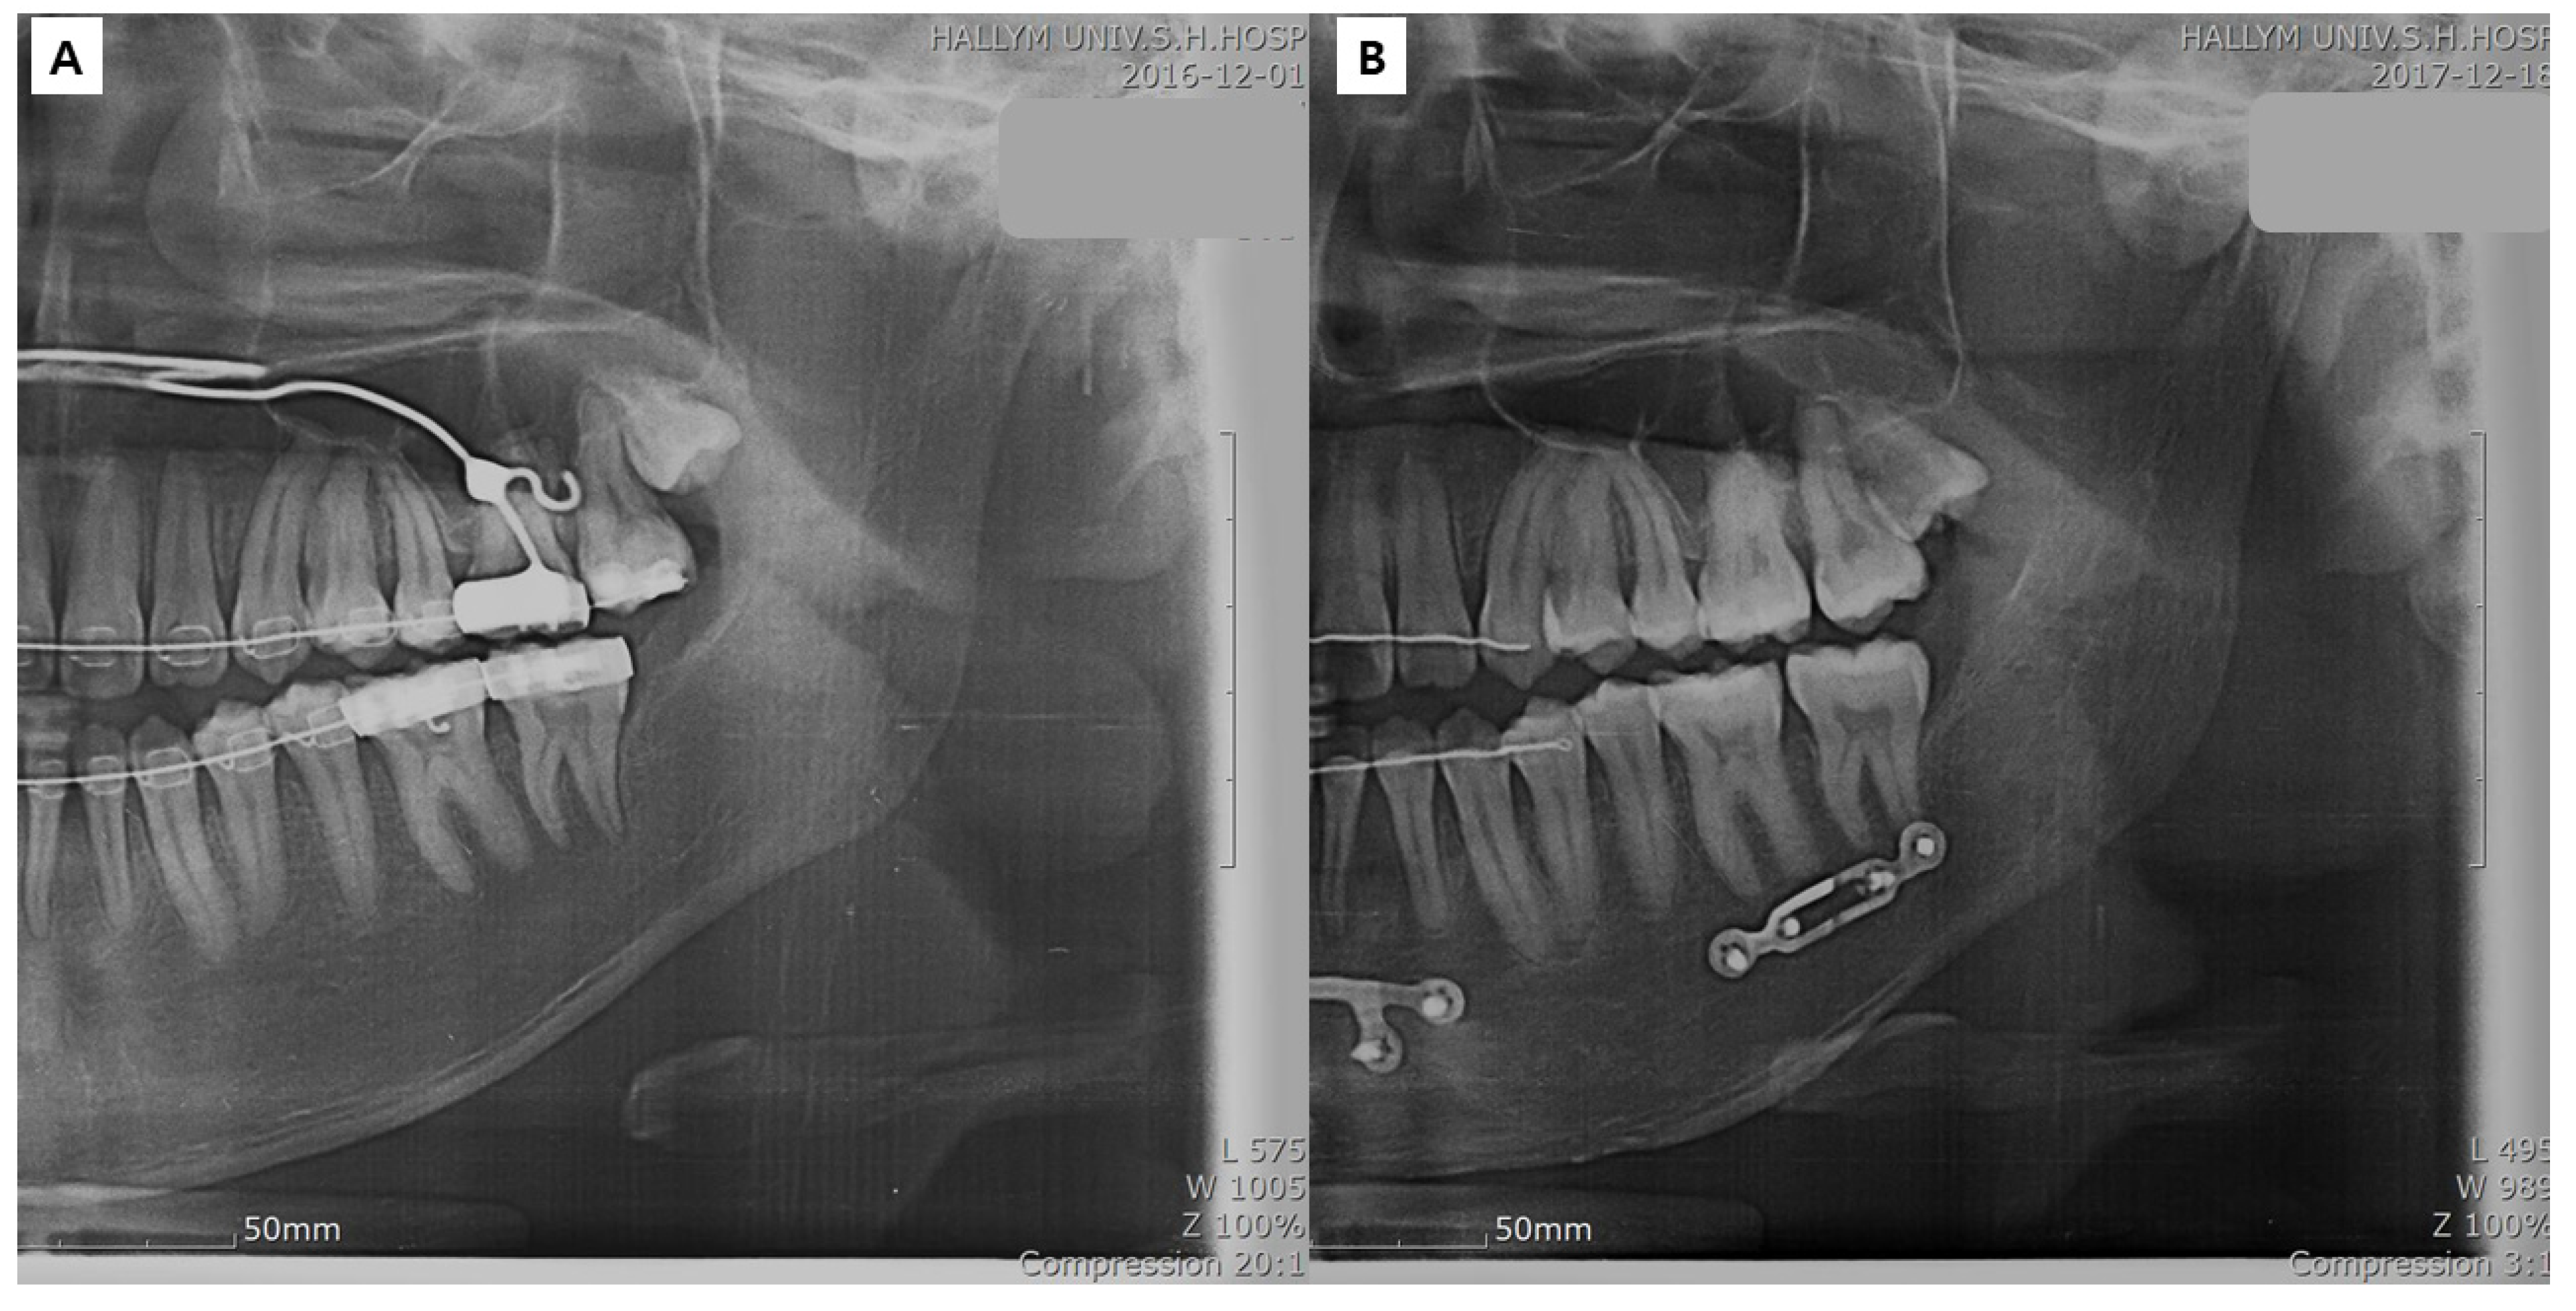

2.2.2. Surgery

2.3. Methods